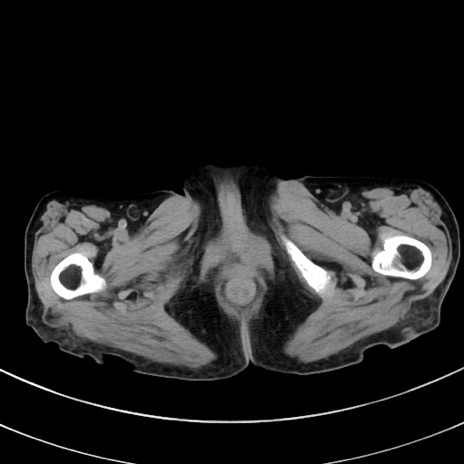

症例33(横断像)

【症例】70歳代 女性

【主訴】心窩部痛

【現病歴】延髄病変の精査・加療にて神経内科入院中。本日より心窩部痛あり。

【身体所見】右下腹部を中心に圧痛と反跳痛あり。

【データ】WBC 10900、CRP 0.02